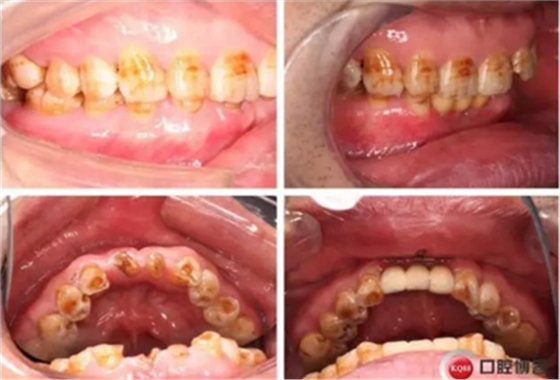

下圖是術(shù)后照片 治療過程 術(shù)前測(cè)量上下牙長(zhǎng)度比例,確定水激光冠延長(zhǎng)深度約3mm,拔除31、41,在術(shù)區(qū)減低牙槽嵴高度,32、42位點(diǎn)種植MINI型一段式種植體,使用臨時(shí)愈合帽行暫時(shí)性修復(fù)。

治療前后照片顯示患者上下臨床牙冠比例協(xié)調(diào),患者對(duì)臨時(shí)修復(fù)體效果十分滿意。當(dāng)然有待后期愈合及長(zhǎng)期的臨床隨訪,以觀察遠(yuǎn)期臨床效果。將水激光應(yīng)用臨床冠延長(zhǎng),有利于精準(zhǔn)去除骨量,利于術(shù)后愈合。而MINI型一段式種植體滿足骨寬度不足,及臨時(shí)修復(fù)打下堅(jiān)實(shí)基礎(chǔ)。